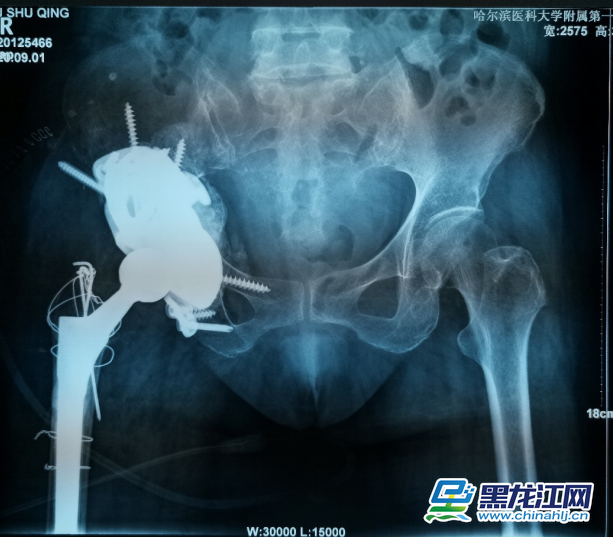

据介绍,70岁的刘阿姨十五年前因股骨头坏死进行了全髋关节置换手术。五年前右腿开始有明显的缩短,髋部疼痛也逐渐加重,来到哈医大一院时已经无法行走。经影像检查,患者十五年前采用水泥固定髋臼杯,金属头和聚乙烯髋臼杯十数年的摩擦产生的聚乙烯碎屑已经导致髋臼巨大的骨缺损,假体上移,不仅髋臼。

患者ct图。